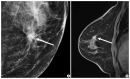

Imaging features of breast cancer molecular subtypes: state of the art

Characterization of breast cancer molecular subtypes has been the standard of care for breast cancer management. We aimed to provide a review of imaging features of breast cancer molecular subtypes for the field of precision medicine. We also provide an update on the recent progress in precision medicine for breast cancer, implications for imaging, and recent observations in longitudinal functional imaging with radiomics.